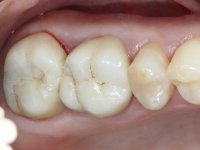

Teeth 17 and 16 were prepared for the fabrication of a 2-element Zr bridge. The impression was performed with a double mixing technique and a monolithic bridge in Zr was made in the laboratory. 4 years later, an abscess appeared in the apical area of tooth 26. It was decided to remove the bridge, remove the intra-radicular posts and retract the endodontic treatments of teeth 17 and 16. The removal of the bridge was carried out by making two cervical cavities. in the palatal area of the bridge and with a microluxator, disinsertion movements were performed. The intra-radicular posts were removed using fine drills and an ultrasound tip. The bridge was provisionally cemented and the patient was referred to a fellow endodontist for endodontic retreatment. After the retreatment, the intraradicular posts were placed again and the bridge was definitively cemented. One year later, a new abscess appears, possibly related to a root fracture. The bridge was sectioned between tooth 27 and 26 and tooth 26 was extracted and the crown of 27 was provisionally cemented. 3 months later, teeth 27 and 25 were prepared and a temporary bridge was made in dual polymerization resin. Then, an impression was made using the double mixing technique and a 3-element bridge in Zr was made in the laboratory. It was permanently cemented in the mouth with resin-reinforced glass ionomer cement.